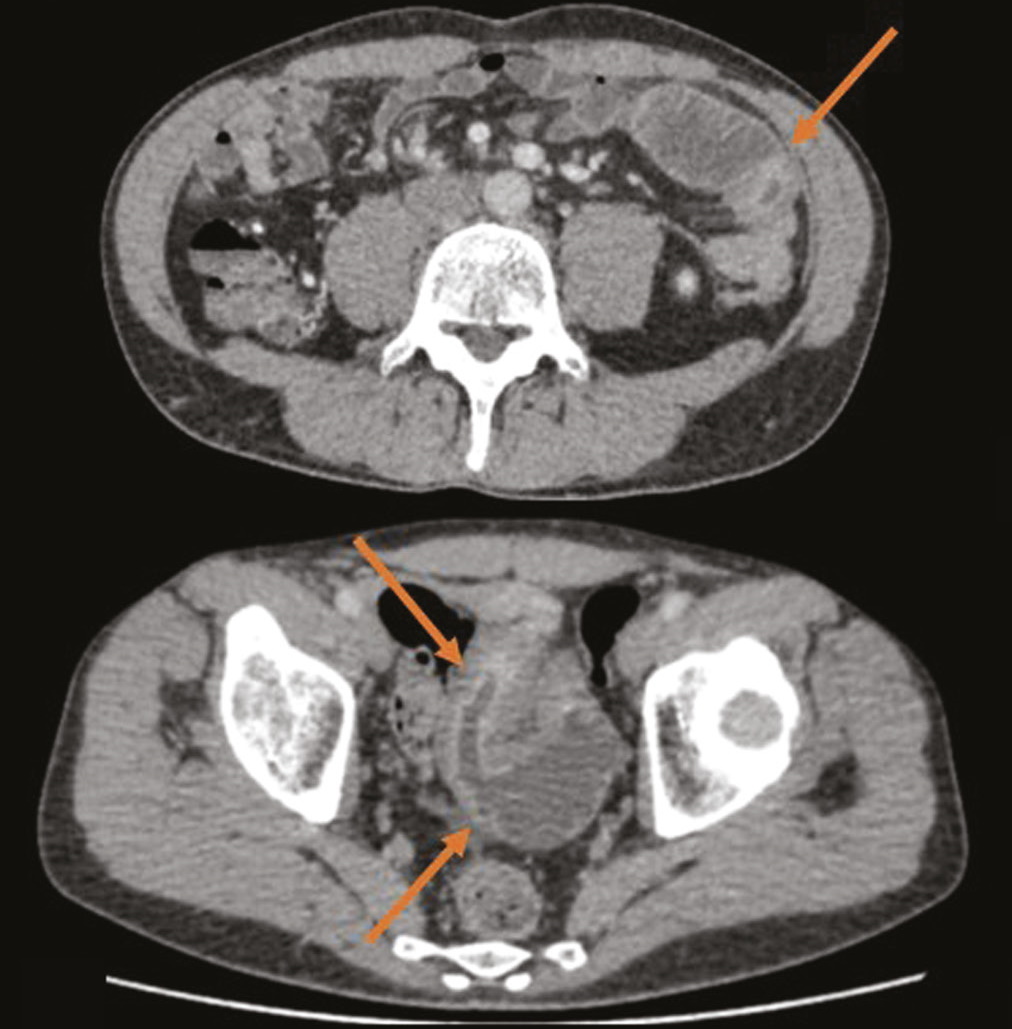

这里描述的是一位临床表现轻微的克罗恩病患者,其小肠和直肠受累,通过使用影像放射学技术验证了其诊断。一名44岁的男子,有轻微腹痛和消化不良。检查显示,有吸收不良的间接迹象,粪便钙蛋白增加;内镜检查与组织学验证显示,有直肠炎的模式。经过计算机断层扫描和磁共振成像肠道造影,可以诊断出小肠的巨大病变,这是症状的基底。

这个临床病例显示了克罗恩病的非典型临床表现,包括空肠、回肠和直肠受累。由于患者没有特征性的主诉,并且由于内窥镜和形态学检查的结果信息量不足,CT和MRI等影像技术在诊断中起到了决定性的作用。